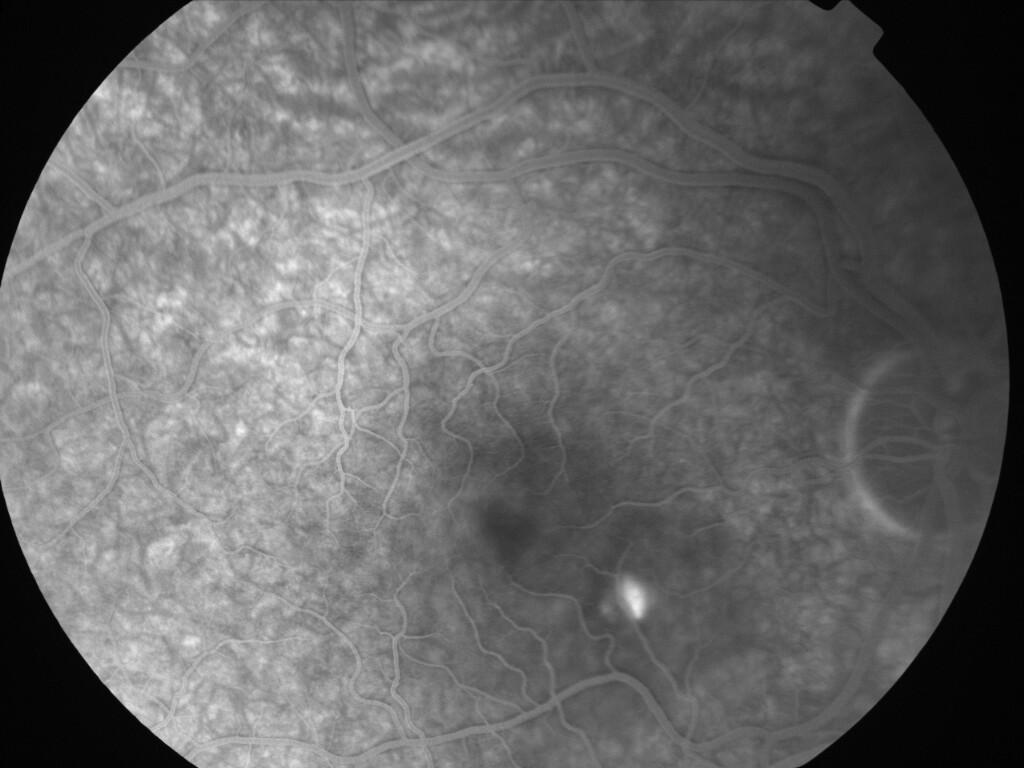

CHORIORETINOPATHIE SEREUSE CENTRALE

IM000003.jpg